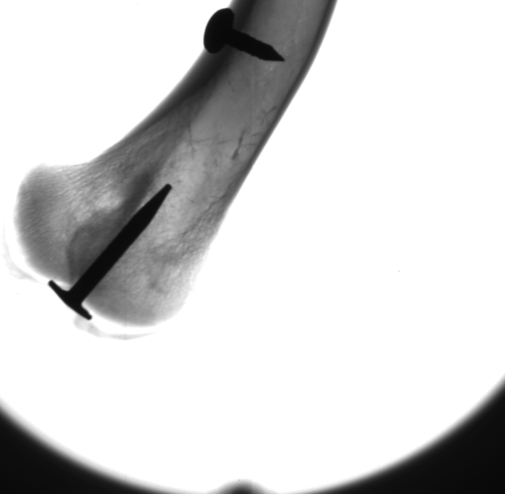

Zum Versuch ROE - Röntgenstrahlung ist zusätzlich eine Lernumgebung verfügbar. Diese besteht aus einem Abschnitt zum physikalischen Hintergrund sowie zum Praktikumsversuch und bietet die Möglichkeit zu Selbsttests.